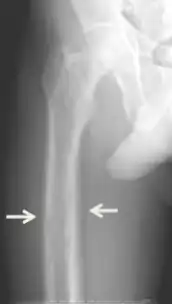

Thinning of long bones due to tertiary hyperparathyroidism

Non-specific symptoms include feeling tired and thirsty; mood changes, including feeling low or depressed, weak and irritable; itching; headache; joint pain; forgetfulness; and abdominal pain.[8][4][9][1] More specific symptoms related to elevated blood calcium and phosphate levels include bone pain or osteodynia and tenderness which are common and related to proximal muscle tenderness. Other signs can include pancreatitis, kidney stones, corneal calcifications, thinning of long bones, and hypodermic calcifications which may be palpable in some patients.[2][4][1]

Conditions due to bone loss such as osteopenia and osteoporosis are common in tertiary hyperparathyroidism along with pathologic fractures. Pseudoclubbing of the digits can also be indicative of a severe tertiary hyperparathyroidism due to excess resorption at the distal phalanges.[8][1]

Diagnosis includes both clinical and laboratory investigations. Radiological investigations include looking for signs of bone loss in both the hands and pelvis which is characteristic of tertiary hyperparathyroidism.[8] Other clinical examination can include grading of muscle weakness, which is done by asking the patient to stand from a seated position with their hands folded across their chest.[4][8] Laboratory investigations include evaluating blood calcium and alkaline phosphatase, which are always increased in tertiary hyperparathyroidism. Other common results from laboratory investigations would include decreased vitamin D levels, elevated blood parathyroid hormone and hyperphosphatemia.[9][8][1][4]